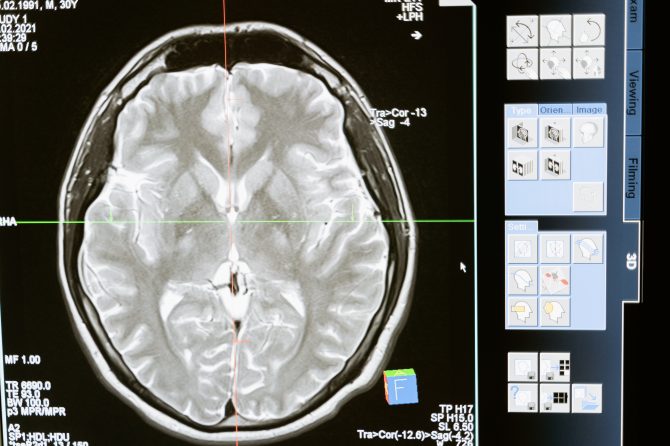

Continua a ser a radiação ionizante que permite captar as imagens, mas é o computador que vai construir o resultado e produzir imagens transversais do corpo. A imagem final é tridimensional.

A aplicação da tomografia aos exames de diagnóstico permite o estudo de seções ou “cortes” transversais do corpo humano. A imagem fornecida é muito mais nítida, uma vez que as estruturas do corpo não estão sobrepostas, permitindo, em simultâneo, distinguir densidades entre tecidos.